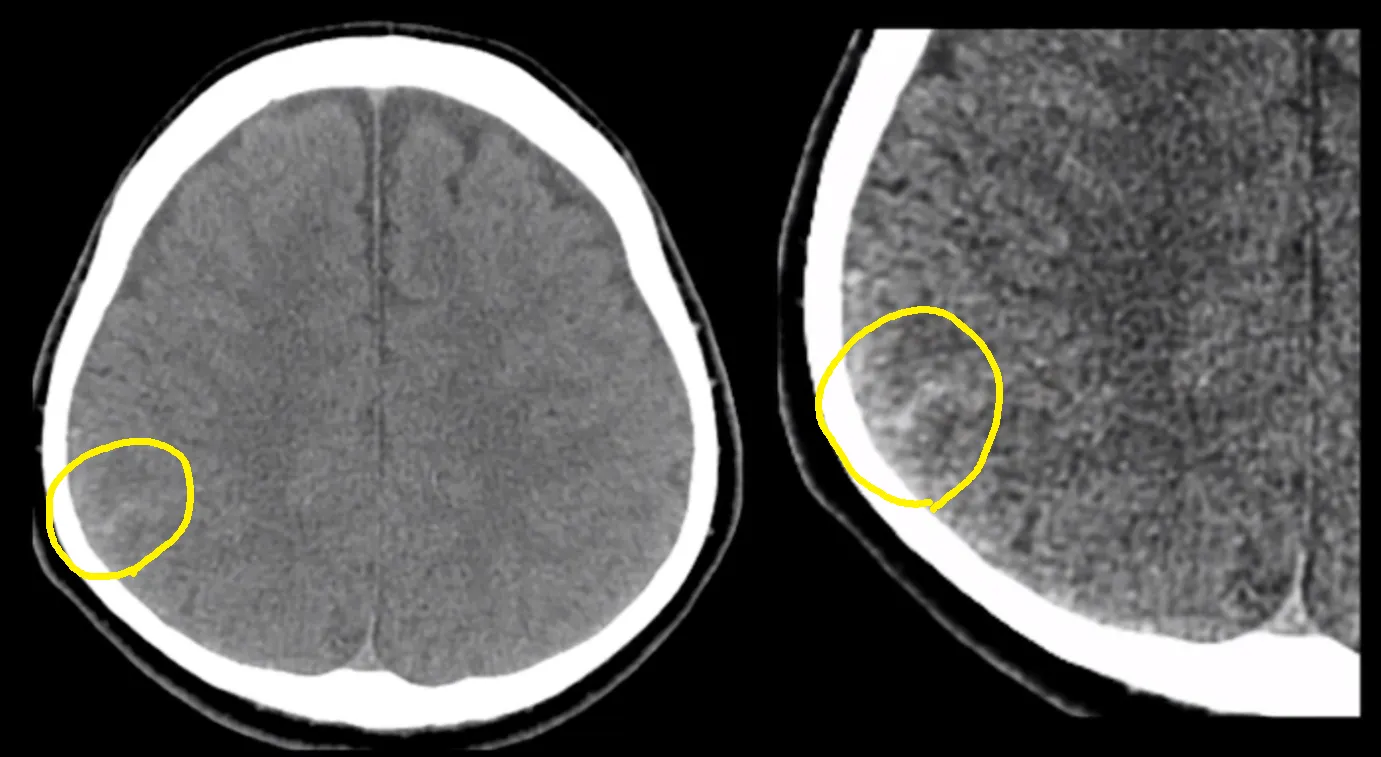

아래 그림과 같이 하나의 sulcus 만 희게 보이는 경우 놓치기가 쉽습니다. 마우스로 window 값을 세밀하게 조정해 가면서 sulcus들을 확인해야 합니다.

minimal traumatic SAH